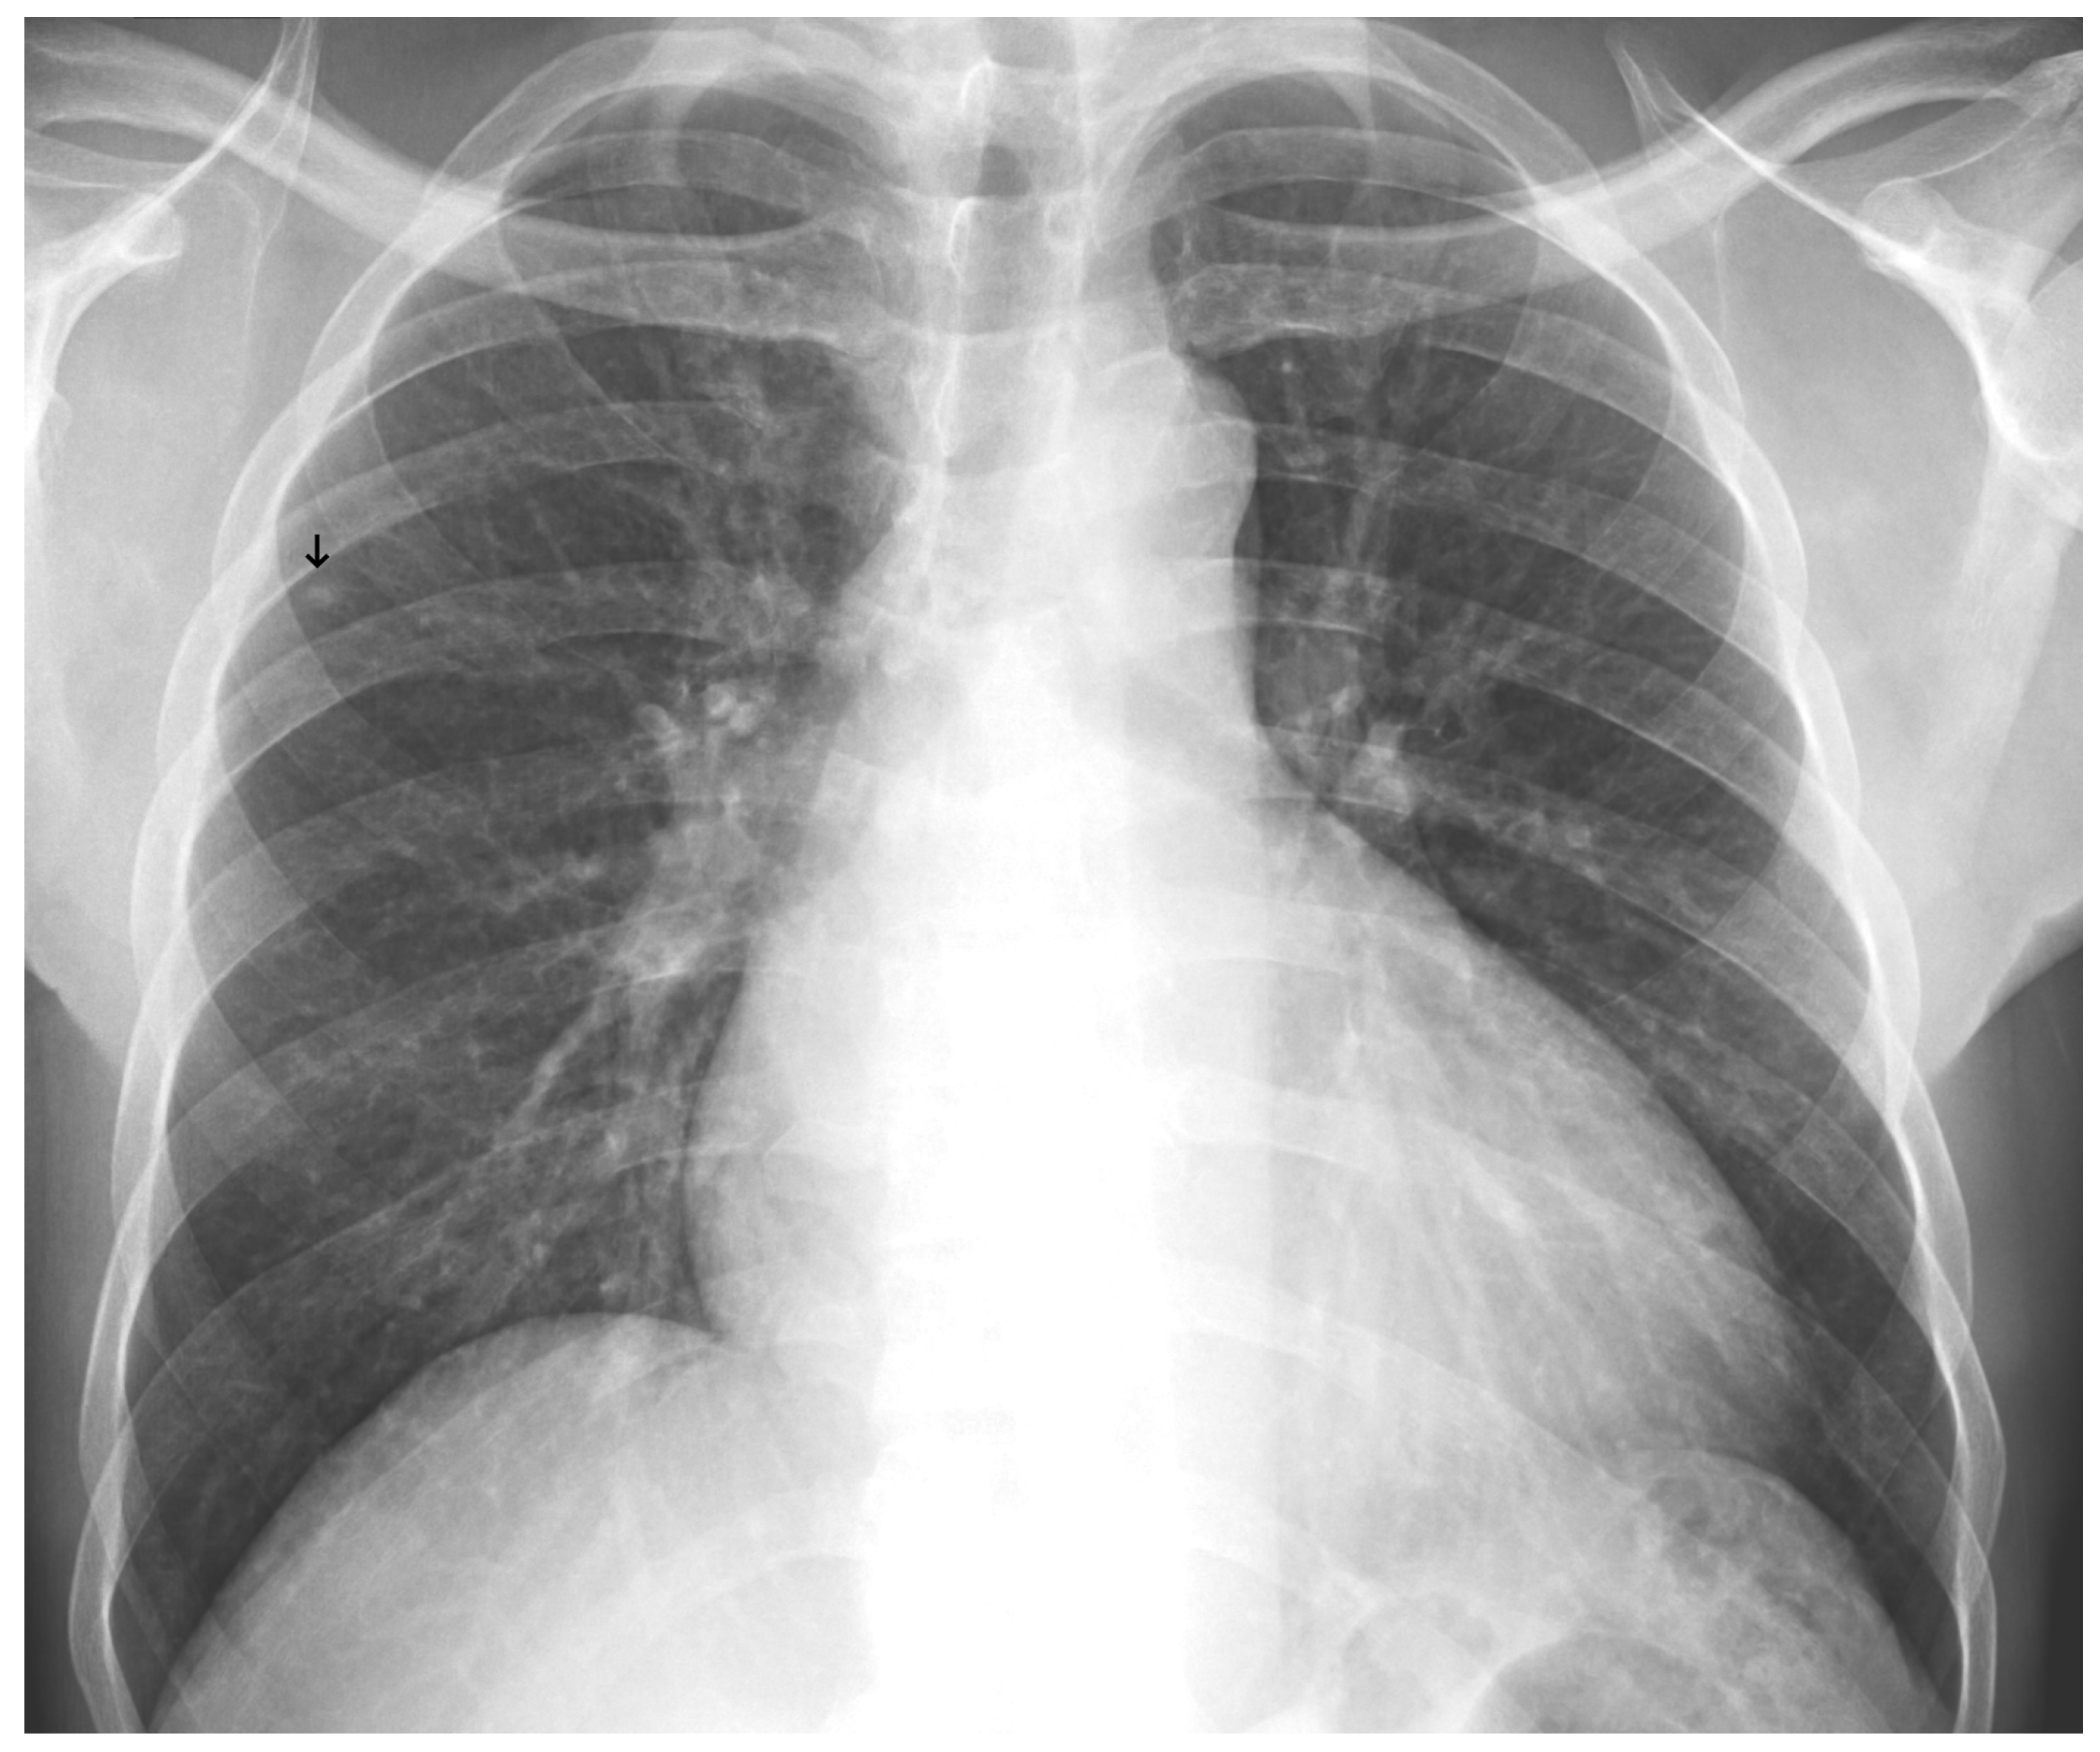

Figure 9. A false negative example of a small, missed nodule (black arrow).

3.3. Error Analysis

An analysis of the algorithm’s false negatives revealed a nuanced performance profile, where a specific miss did not always equate to a complete system failure. Across the board, a substantial number of cases with a false negative for a particular pathology were nevertheless correctly identified as abnormal by the general “yes-finding” classifier or had other co-occurring true positive pathologies. For example, out of 38 false negatives for opacity, the algorithm correctly identified the exam as abnormal in 25 cases. In many instances of a missed finding, the algorithm successfully detected other pathologies within the same study. Misclassification was another notable source of error, where an existing pathology was detected but incorrectly labeled, such as opacities being predicted as masses or nodules (Figure 4). Radiologist review of these false-negative cases frequently noted findings that were “subtle,” “small,” “doubtful,” “seen on lateral image only,” or “non-specific.” In other cases, the algorithm correctly identified a more critical finding, like a large pleural effusion, while missing a secondary, less significant pathology (Figure 3). Figure 9, Figure 10 and Figure 11 illustrate false negative cases for opacity, pneumothorax, and nodule, respectively. This highlights the inherent limitations and inevitable failures of this kind of system.